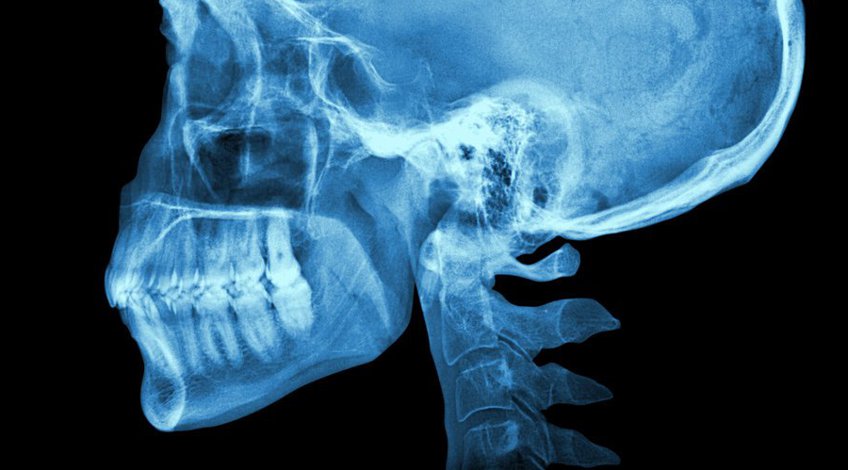

Radiografías, Imagenes de Cráneo

Una radiografía del cráneo es una imagen de los huesos que rodean el cerebro, entre ellos, los huesos faciales, la nariz y los senos paranasales. Este tipo de radiografía es la que le va a ordenar su médico en caso de haber sufrido una lesión en la cabeza o muestra síntomas de una afección relacionada con el cráneo.

Pueden buscar afecciones como tumores, infecciones de los senos nasales o del oído, fracturas, pérdida ósea o movimiento de tejidos blandos dentro del cráneo.